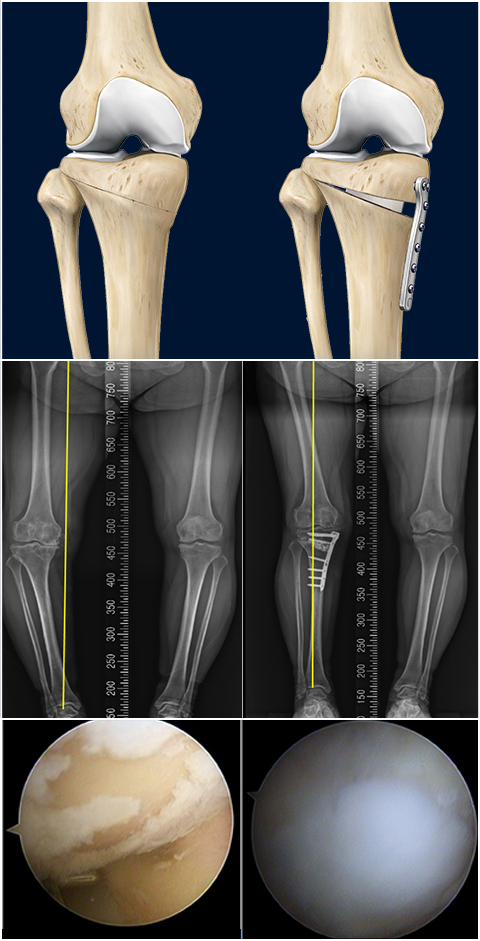

근위경골절골술은 오다리 변형으로 인해 무릎 안쪽 관절에 집중되는 체중 부하를 교정하기 위한 수술입니다.

무릎 아래 뼈인 경골의 정렬축을 조정하여, 이를 통해 무릎 안쪽 연골에 집중되던 부담을 줄이고 통증 완화를 기대할 수 있습니다.

마치 오래된 자동차 타이어에 편마모가 생기면 위치를 교환하여 사용 수명을 늘리는 것과 같은 원리입니다.

여기에 연골의 근본적인 재생을 유도하는 줄기세포(카티스템) 연골재생술을 결합한다면 무릎 관절의 수명을 늘리는데 더욱 도움이 됩니다. 결과가 좋은

환자분의 경우에는 평생 무릎 인공관절을 안하는 경우도 있을 정도로 예후가 우수한 치료법입니다.